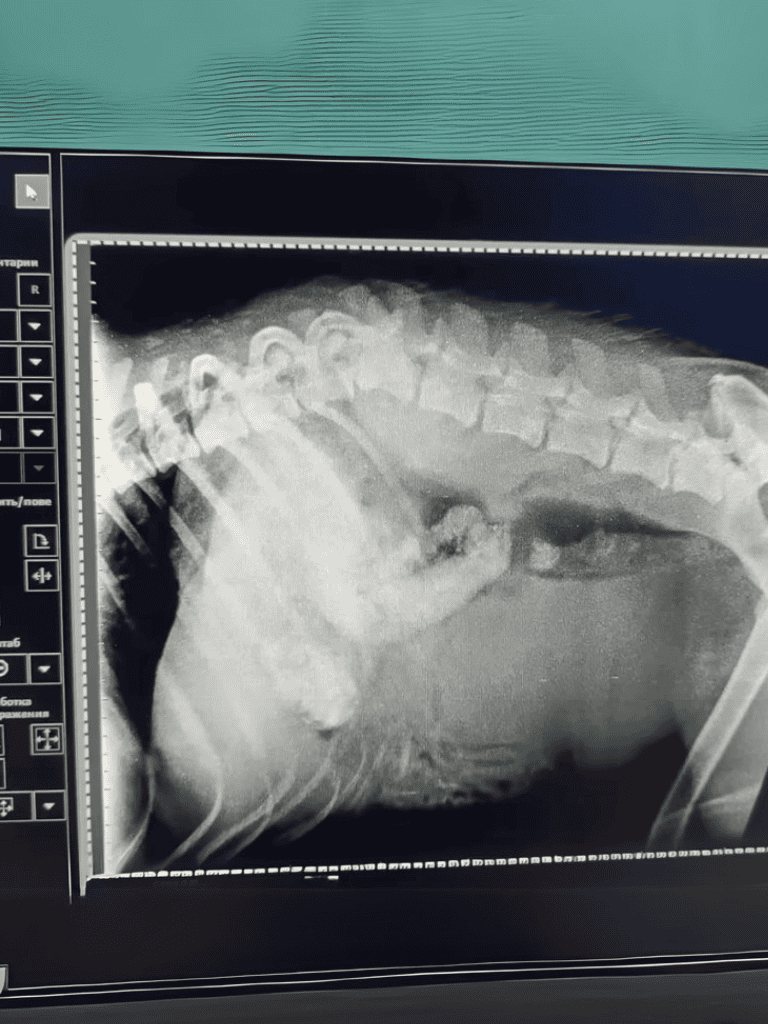

At the veterinary clinic, the tests revealed sobering news: the poor dog’s spine was broken, most likely the result of an unfortunate accident.

Despite the dire diagnosis, its vital signs remained stable, a small beacon of hope amidst the dismal circumstances.

The chances were daunting—a mere 1% possibility that Graf might walk again. The veterinary team prepared to operate, aiming not to restore movement but to alleviate the pain.

Encased in his new metallic support, Graf’s spine was carefully stabilized after the complex procedure.